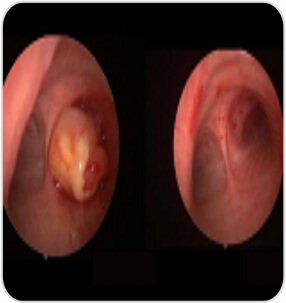

Bronchoscopy revealed near complete occlusion of the right main bronchus with a mass. Tumor was arising from the right lower lobe- basal segment. She was intubated with rigid bronchoscope and the tumor debulking was done with electrosurgical snare and 1.1 Cryo Probe. Post procedure complete patency of right bronchus was achieved. Patient’s symptoms improved after the procedure

Tumor debulking by a cryo probe

Before After